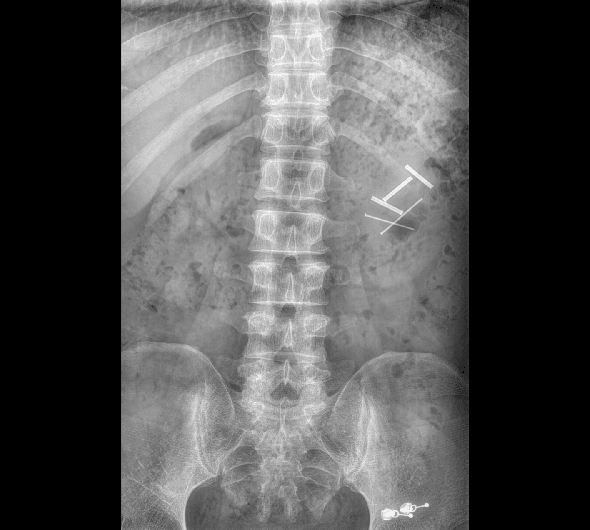

原厂优质影像链,搭载直接生长式碘化铯非晶硅平板,带来更加清晰锐利的图像效果。